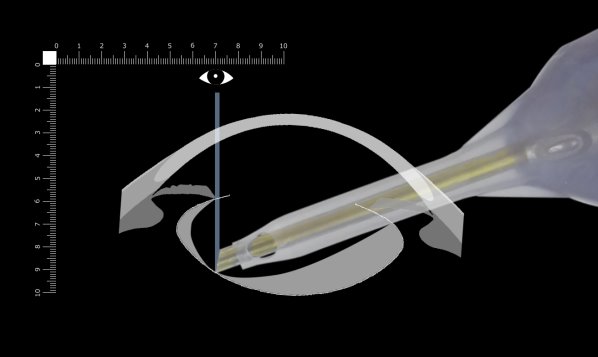

ここでは側面画像から考えます。

ベベルが良く見えないときは眼球を上転すると見やすくなります。